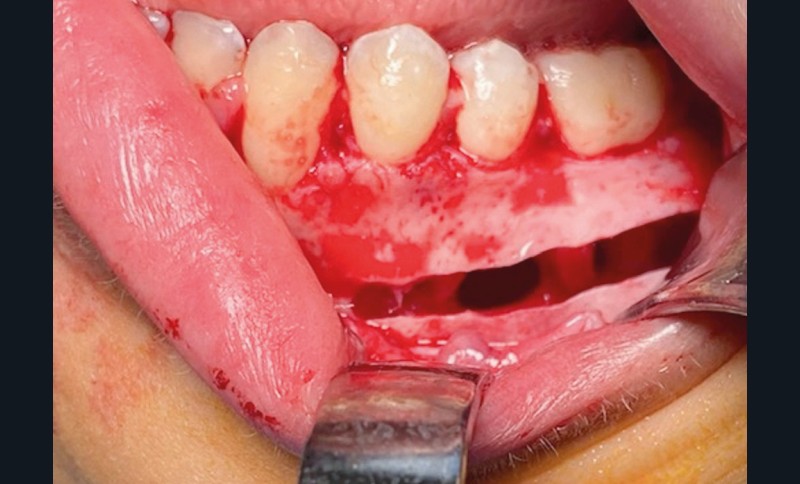

Le diagnostic est fait lors de l’intervention : la cavité est « vide », ne contenant aucune poche kystique (fig. 5).